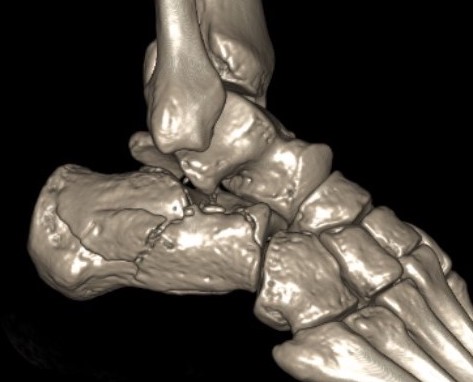

Fracture patterns

| Primary fracture line | Secondary fracture lines |

|---|---|

|

Lateral process of talus driven into crucial angle - starts at lateral wall near tarsal sinus - passes obliquely across posterior facet - exits at medial wall posterior to sustentaculum tali |

Passes immediately behind the posterior facet of the subtalar joint - exits posterior to posterior facet & anterior to tendoachilles insertion - creates thalamic portion containing posterior facet |

Common fracture fragments

| Sustenacular | Superolateral | Lateral wall | Posterior tuberosity |

|---|---|---|---|

| Superomedial |

Lateral fragment of posterior facet

|

Tongue fracture | |

| Attached to talus by deltoid ligament | Thalamic fragement | Secondary fracture line exits below tendoachilles |